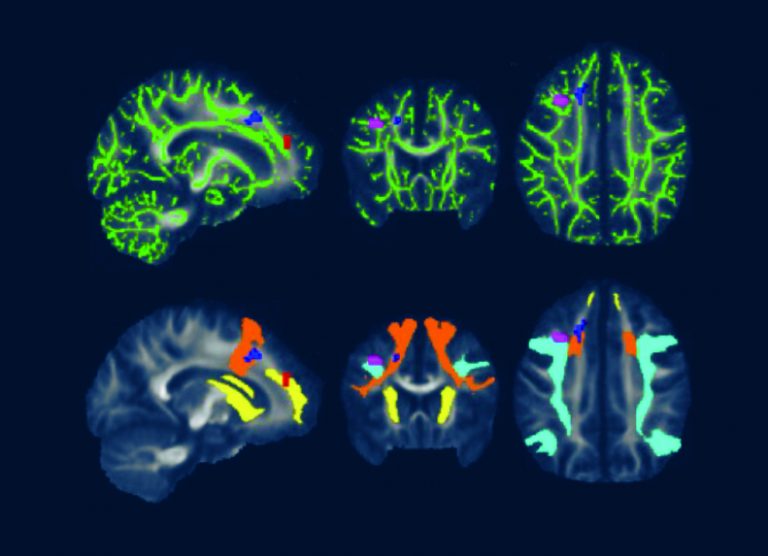

Advanced Brain Imaging Shows Lyme Disease Brain Fog is Real Johns Lymes Disease Brain Fog Lyme disease can also affect your brain and cause brain fog. More than 1 in 10 people successfully treated with antibiotics for lyme disease go on to develop chronic, sometimes debilitating, and poorly understood symptoms of. Brain fog is commonly experienced by lyme disease patients but difficult to detect because cognitive deficits can be too subtle for standard diagnostic tests. Lymes Disease Brain Fog.

Advanced imaging shows Lymerelated brain fog is real Lymes Disease Brain Fog Brain fog is commonly experienced by lyme disease patients but difficult to detect because cognitive deficits can be too subtle for standard diagnostic tests to uncover. Discover how you can deal with brain fog along with the other symptoms of. More than 1 in 10 people successfully treated with antibiotics for lyme disease go on to develop chronic, sometimes debilitating,. Lymes Disease Brain Fog.

Is Lyme Disease Associated Brain Fog Real? Johns Hopkins Lyme Disease Lymes Disease Brain Fog Brain fog is commonly experienced by lyme disease patients but difficult to detect because cognitive deficits can be too subtle for standard diagnostic tests to uncover. More than 1 in 10 people successfully treated with antibiotics for lyme disease go on to develop chronic, sometimes debilitating, and poorly understood symptoms of. Discover how you can deal with brain fog along. Lymes Disease Brain Fog.

From pubs.rsna.org